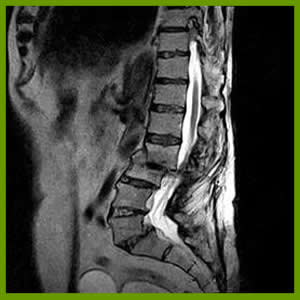

En qué consiste la RMN de columna ?

La resonancia magnética nuclear (RMN) es un examen médico no invasivo que ayuda a que los médicos diagnostiquen y traten enfermedades.Nuestro servicio cuenta con tecnología de vanguardia, con software especial para cada región del cuerpo, en especial para columna, contamos con un programa llamado COMPOSING que nos permite obtener los tres tramos de la columna en una solo adquisición.Las imágenes detalladas obtenidas con la RMN les permiten a los médicos evaluar mejor varias partes del cuerpo y determinar la presencia de ciertas enfermedades que no se podrían evaluar adecuadamente con otros métodos por imágenes como los rayos X, el ultrasonido o las tomografías axiales computarizadas (también denominadas TC o exploración por TAC).El examen de RMN de columna muestra la anatomía de las vértebras que conforman la columna, así como los discos, la médula espinal y los espacios entre las vértebras por donde pasan los nervios.En la actualidad, la RMN es el examen de diagnóstico por imágenes más sensible que se utiliza en la práctica médica de rutina para visualizar la columna.

• Evaluar los discos—protuberantes, degenerativos o hernia de disco intervertebral—una causa común de dolor lumbar y ciática.

• Evaluar los nervios comprimidos (pinzados) e inflamados.

• Explorar las posibles causas en pacientes con dolor lumbar (por ejemplo, fractura de compresión).

• Visualizar la infección de la columna o tumores que aparecen en la columna o se han extendido a ella.

• Las imágenes de RMN de la columna son más claras y detalladas que las que se obtienen con otros métodos de diagnóstico por imágenes. Esto hace de la RMN una herramienta valiosísima para el diagnóstico y evaluación tempranos de muchas patologías de la columna, incluyendo tumores.

• Se ha comprobado que la RMN es una herramienta valiosa para el diagnóstico de una amplia gama de patologías, incluyendo, entre otras, las patologías congénitas, enfermedades crónicas de la columna vertebral (por ejemplo, la esclerosis múltiple), anomalías óseas (por ejemplo, fracturas), enfermedades de disco (por ejemplo, hernia de disco), anomalías vasculares y tumores.

• La RMN muestra anomalías, lesiones y enfermedades en la zona de la columna que no pueden visualizarse con otros métodos de diagnóstico por imágenes.

• La RMN es muy útil para evaluar lesiones en la columna. Es particularmente útil para diagnosticar o descartar la compresión de la médula espinal cuando el examen clínico revela debilidad muscular o parálisis.

• La RMN puede detectar pequeños cambios en la columna vertebral que podrían ser una infección o un tumor en etapa temprana. El procedimiento es mejor que la exploración por TAC para la evaluación de tumores, abscesos y otras masas de tejido blando cerca de la médula espinal.